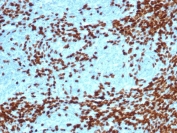

IHC staining of FFPE human thymoma with recombinant TdT antibody (clone DNTT/4617R). HIER: boil tissue sections in pH 9 10mM Tris with 1mM EDTA for 20 min and allow to cool before testing.

IHC staining of FFPE human thymoma tissue with recombinant TdT antibody (clone DNTT/4617R). HIER: boil tissue sections in pH 9 10mM Tris with 1mM EDTA for 20 min and allow to cool before testing.